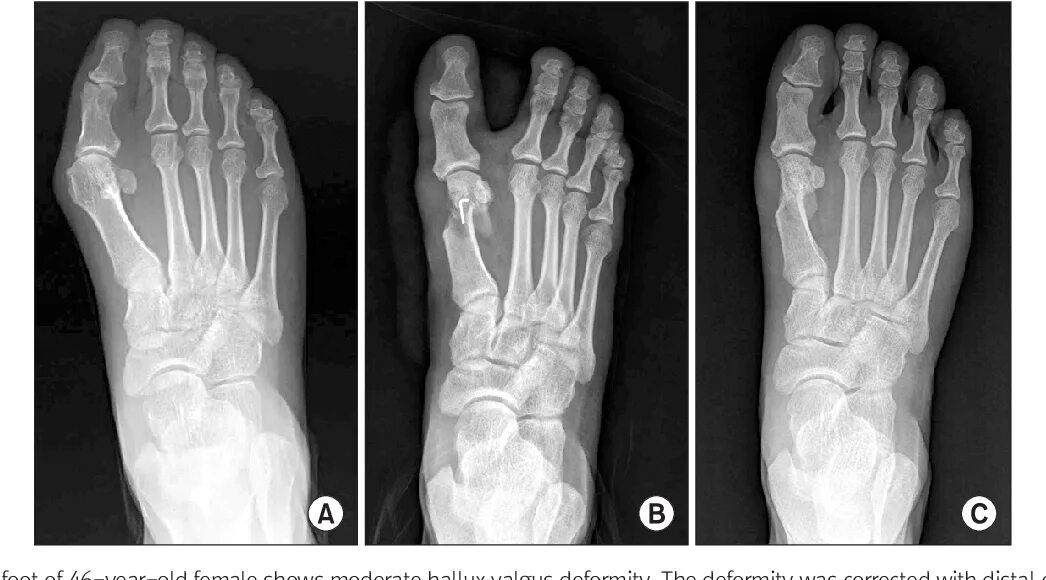

Пяточная остеотомия